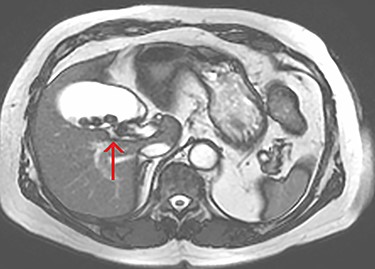

The tubular structure was remote from the porta hepatis with one lumen. It was located within the distal gallbladder fossa. Inspection of the gallbladder demonstrated an opening at the same orientation and of the same calibre as this tubular structure, raising suspicion for a duplicated cystic duct. Probing the source of the bile leak confirmed a single lumen. The capacity to perform IOC was not available at the time of the operation. A review of the patient’s prior imaging was performed. Recent cardiac magnetic resonance imaging (MRI), while not dedicated magnetic resonance cholangiopancreatography (MRCP), provided adequate views of the liver, gallbladder and biliary tree to demonstrate the suspected anomaly. On these images, two structures were seen to be connecting the gallbladder to the biliary tree. One duct was observed at Hartmann’s pouch, while a second connected to the gallbladder body (Fig. 1, Fig. 2). The images confirmed suspicion of a duplicated cystic duct and the decision was made to clip the lumen. The cholecystectomy was completed and a drain placed in the gallbladder fossa.

Axial view of the liver and gallbladder from a cardiac MRI showing a tubular structure entering the gallbladder at the level of the body in keeping with an accessory cystic duct (highlighted by the arrow).